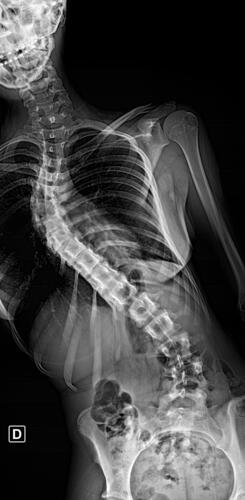

A Vá tem 13 anos e precisa urgentemente realizar uma cirurgia na coluna.Valentina foi surpreendida com o diagnóstico de escoliose hepática grave com 67 graus de desvio (desvio longitudinal da coluna), e precisa realizar com urgência a cirurgia corretiva, os exames foram realizados em Porto Alegre, mas a cirurgia está marcada para dia 13/07 em São Paulo devido a gravidade do caso, para isso a família terá que ficar residindo próximo ao hospital em São Paulo por no mínimo 30 dias para uma plena recuperação. Sabemos bem que qualquer procedimento cirúrgico é delicado, na coluna então nem se fala.Após o diagnóstico e o prognostico dessa doença a família se desfez de alguns bens (carro e moto) para cumprir os prazos dos exames e consultas, necessitando agora arrecadar o valor para a estadia da pequena Valentina e seu pós operatório (medicação, consultas e fisioterapia).

Em anexo os exames (laudo e imagens) para expressas a gravidade do caso.